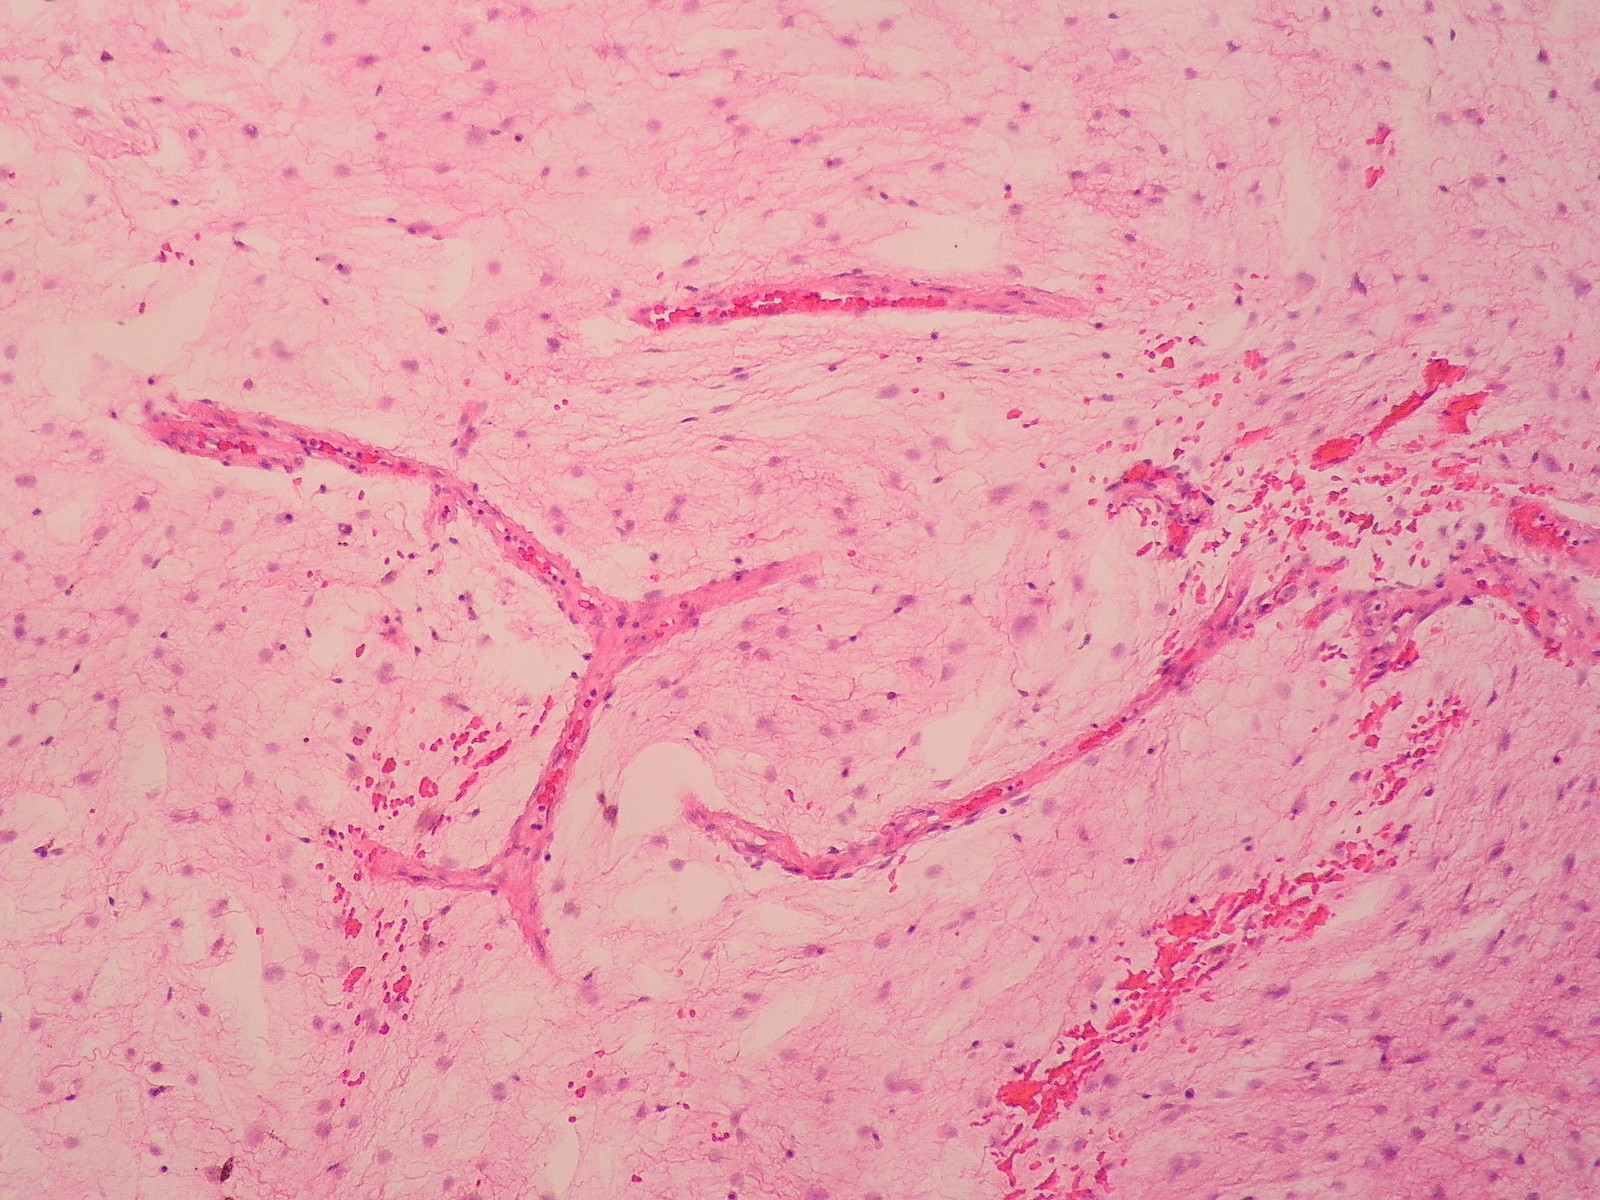

Microscopic (histologic) description

- Low to moderately cellular, bland fusiform or spindled cells with focal to diffuse whirling in heavily collagenized stroma with abrupt transition to myxoid areas

- 45% have epithelioid areas

- 40% contain poorly formed but large collagen rosettes

- Often infiltrates adjacent skeletal muscle

- Occasionally has areas of increased cellularity, atypia, necrosis or mitotic activity characteristic of intermediate to high grade sarcoma

- Recurrences may show increased cellularity and mitotic activity

Microscopic (histologic) images